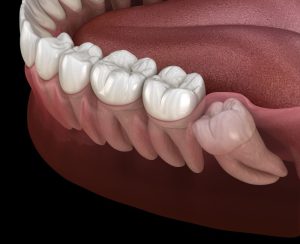

As wisdom teeth begin to erupt, they can push against adjacent teeth, causing them to move and shift. This movement may lead to crowding or misalignment in the mouth, resulting in discomfort in the jaw. Symptoms that could arise from this displacement include pain, swelling, and stiffness, which may make it challenging to open the jaw and even affect one’s ability to breathe comfortably.

In some cases, wisdom teeth may only partially emerge, leaving a flap of gum tissue covering the tooth. This flap can trap food particles and bacteria, leading to gum infections, further exacerbating the pain and swelling. Impacted wisdom teeth, where the tooth does not have enough space to emerge correctly, can also be a source of discomfort. Impacted teeth may grow at an angle, pressing against other teeth, and potentially causing damage to the surrounding dental structures.